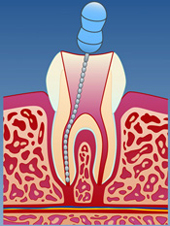

Inne i tannen er det et hulrom med nerver og blodkar kalt pulpa. En rotfylling innebærer at pulpa renses bort og erstattes med et bakterietett materiale. Behandlingen strekker seg vanligvis over minimum to tannlegebesøk. Selve inngrepet skjer under lokalbedøvelse og er vanligvis smertefritt. Etter at tannen er ferdig rotfylt, kan den bygges opp igjen. Dette gjøres med en tannfarget fylling eller en keramisk krone (porselen).

Dersom pulpa blir skadet og infisert av bakterier, kan den ikke tilhele. Den vanligste årsaken til slike skader er dype hull i tannen (fig. I). Resultatet kan bli tannsmerter, og en infeksjon som sprer seg til kjevebenet rundt tannens røtter (fig. II). En rotfylling innebærer fjerning av bakteriene slik at en får kontroll på infeksjonen (fig. III). På denne måten kan tannen reddes (fig. IV).

| figur I | | figur II | | figur III | | figur IV |